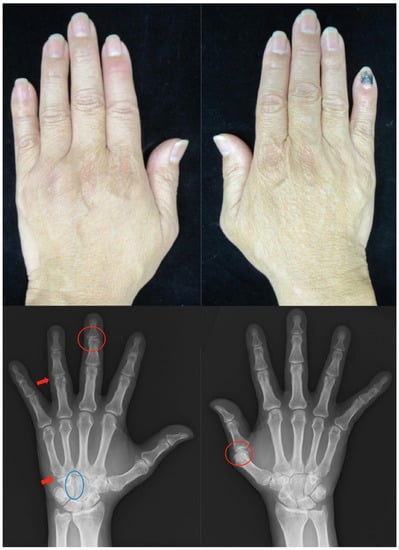

Patient: Man in his 50s